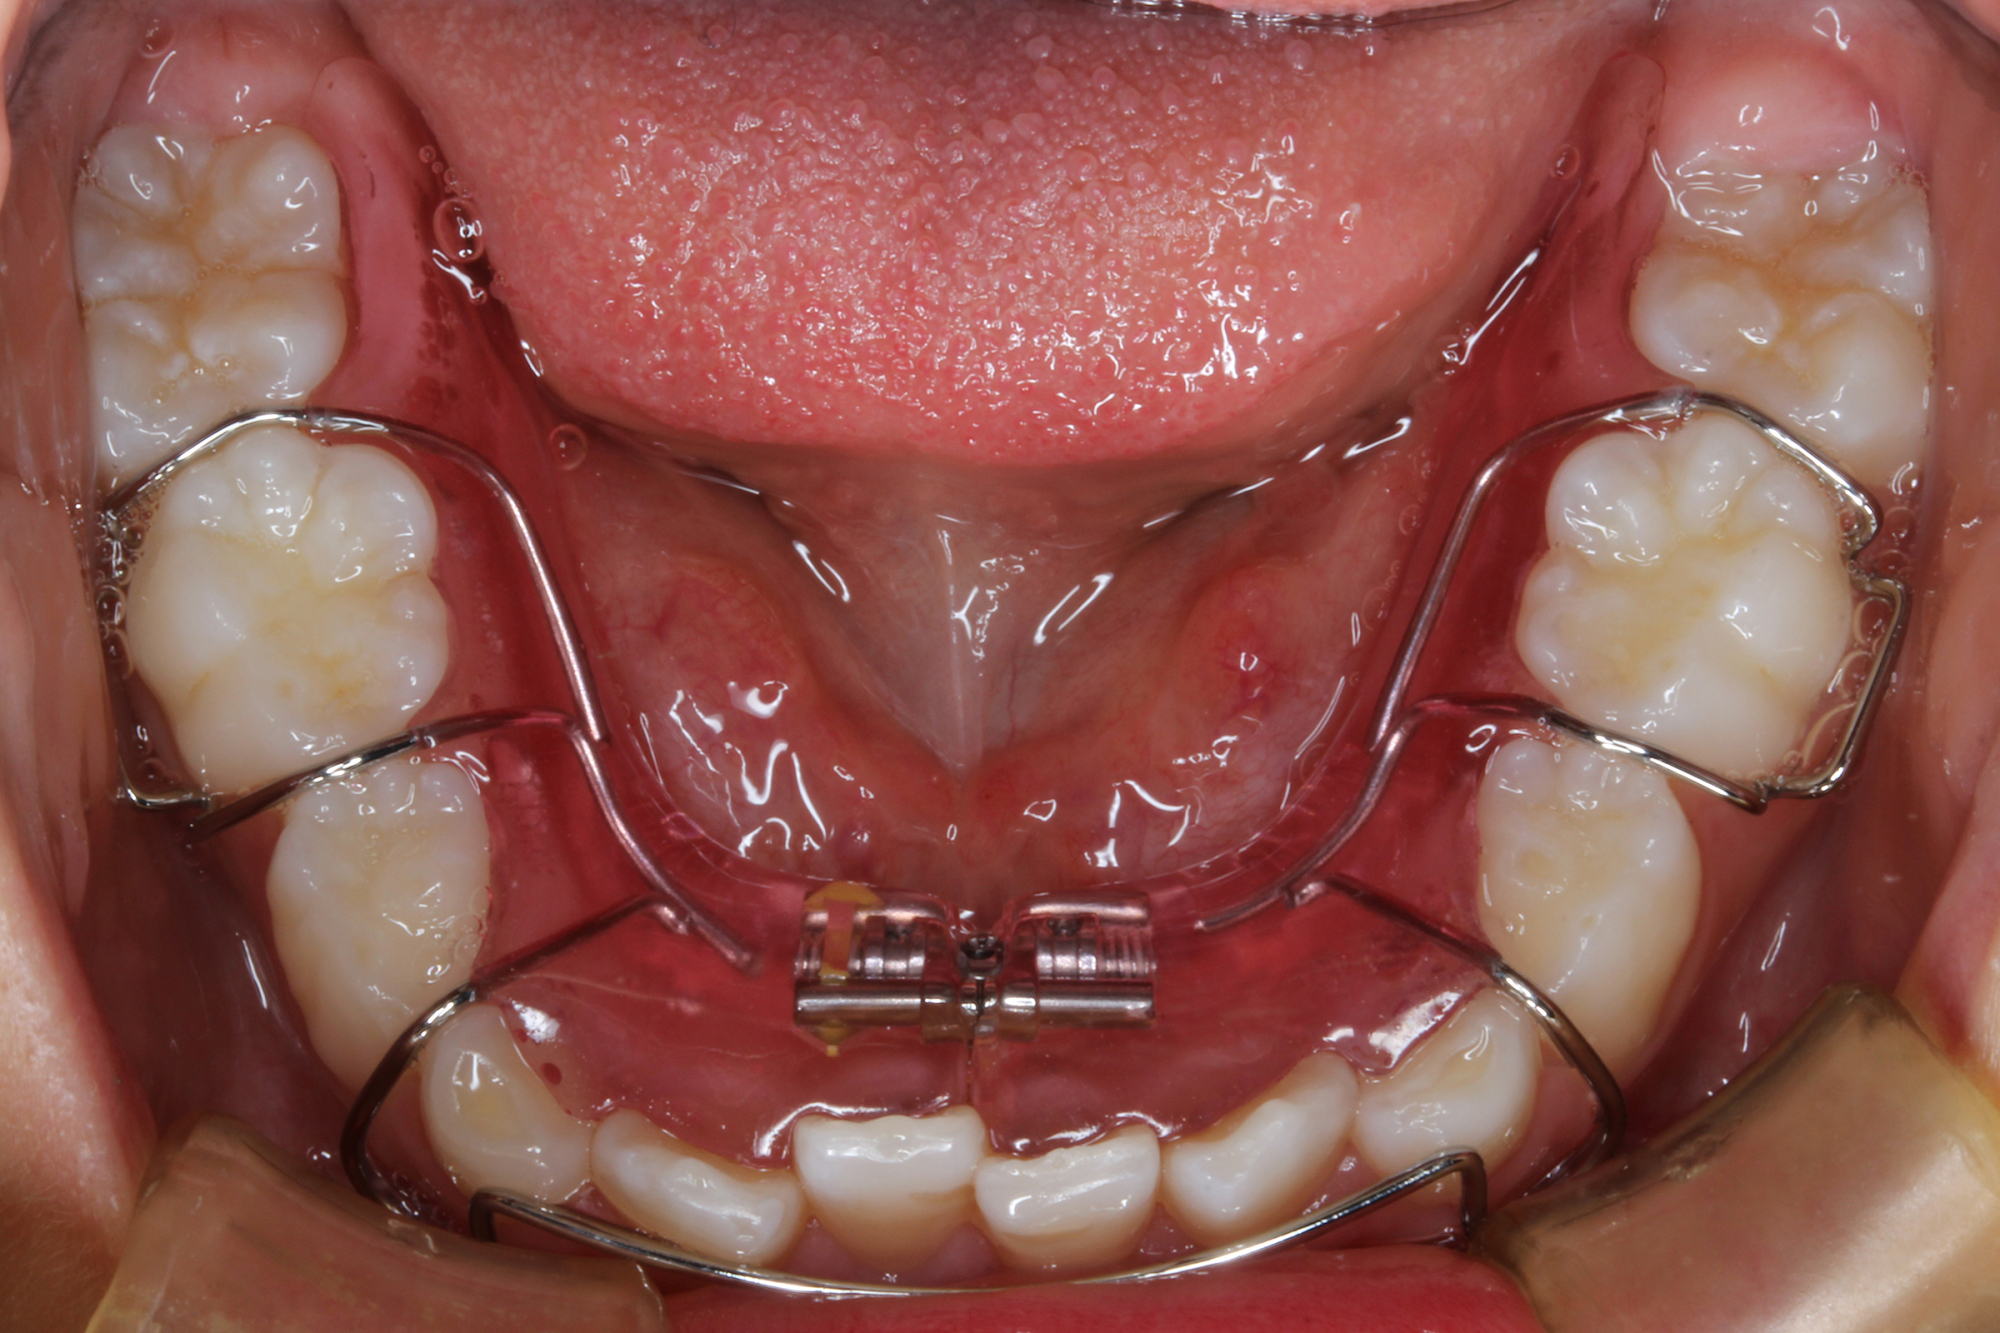

日本で行われている拡大床治療にも色々な方法がありますが当院での特長は最初に永久歯に生え替わる上下4本の前歯を奥歯の生え替わりが始まる前までに顎を拡大してきれいに並べることです。そのため拡大床治療の期間は小学校1年生頃から4、5年生頃までの間に限定しており、それまでに目的が達成できない場合には別の治療法に移行します。またゆっくりスペースを獲得するようにしているのも特長で2週間に1回ネジを回すようにしています。一般的には1週間にⅠ回ないし2回ネジを回すことが多いようです。ゆっくり進めるので一日の装着時間はお家にいるときと寝ている間だけにしています。学校や自宅以外での装着はせずゆっくり拡大していくので治療期間が長くなりますが後戻りは少なく確実になります。治療開始時期が大切ですので時期を逸した場合には拡大床治療は行いません。一般的に拡大床治療の評判が悪いのは開始時期が遅く、いつまでも治療を長引かせ治らないことによるものが多いようです。 拡大床治療はスペースを作って永久歯がならぶスペースを作ることが目標ですので細かい歯の向きや角度まで整えられないこともあります。そんな場合には別の矯正治療が必要になります。

拡大床治療で顎のスペースを拡げられるのは11歳くらいまでです。そのため個人差はありますが遅くても小学校2年生までに始めなければなりません。下の前歯が生え替わりはじめた頃から下の前歯が4本、上の前歯が2本生え替わる頃までが始め時です。すでに上下4本とも生え替わってしまった場合にはすでに遅いことが多くあります。